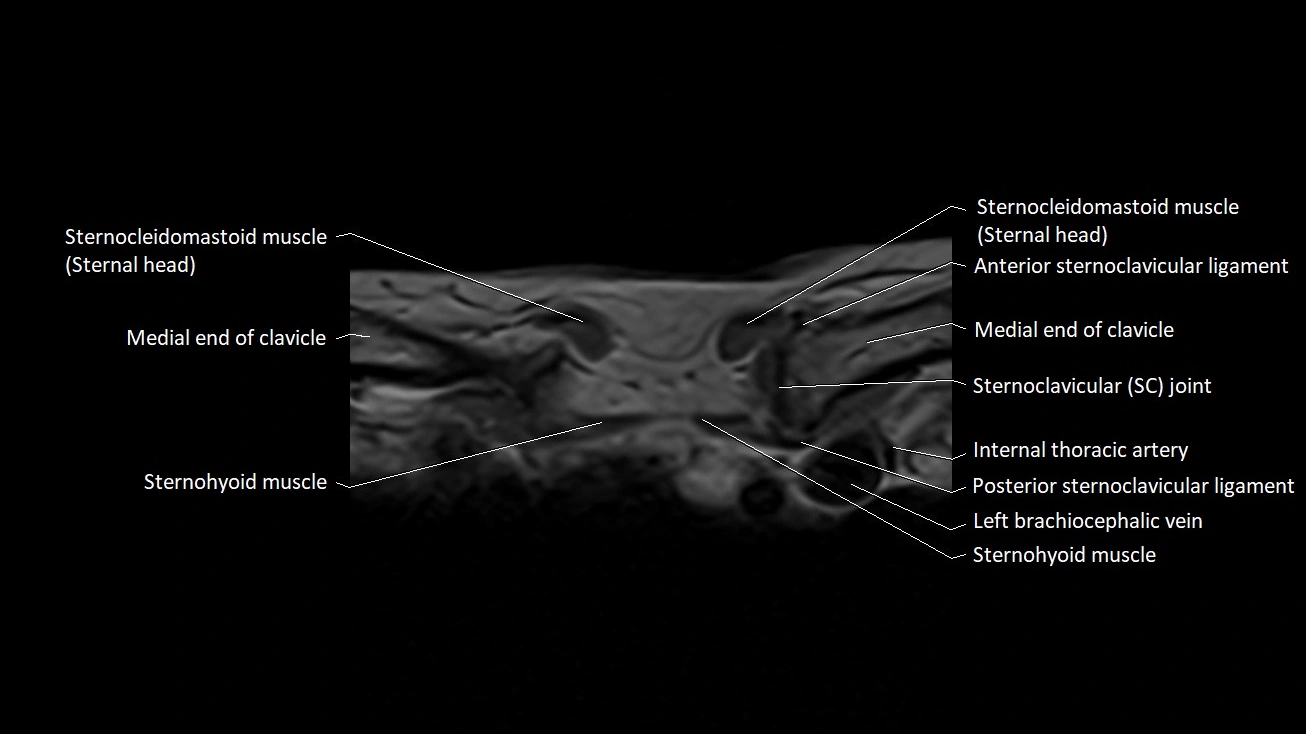

Anterior sternoclavicular ligament

The anterior sternoclavicular ligament (ASCL) is the thickened anterior portion of the joint capsule of the sternoclavicular (SC) joint, reinforcing the articulation between the sternal end of the clavicle and the manubrium of the sternum. As one of the key stabilizers of the SC joint, it prevents excessive anterior and superior translation of the clavicle during upper limb movement.

The ligament spans obliquely from the anterior surface of the manubrium to the anterior aspect of the medial clavicle. Its strength is essential for shoulder girdle stability, as the SC joint serves as the only true synovial articulation connecting the upper limb to the axial skeleton.

Location and Structure

• Position: Lies on the anterior surface of the sternoclavicular joint, connecting the manubrium to the sternal end of the clavicle.

• Orientation: Runs obliquely superolaterally from the sternum toward the clavicle.

• Composition: Dense fibrous connective tissue forming the anterior reinforcement of the SC joint capsule.

• Thickness: Broad and strong, blending with the surrounding capsule and interclavicular ligament superiorly.

Relations

• Anteriorly: Skin, superficial fascia, sternocleidomastoid muscle (sternal head).

• Posteriorly: SC joint capsule, articular disc, and synovial space.

• Superiorly: Interclavicular ligament.

• Inferiorly: Manubrial surface and upper costoclavicular region.

• Laterally: Medial clavicle.

• Medially: Manubrium of the sternum.

MRI images

image